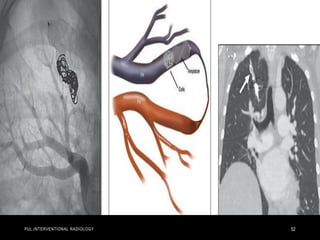

• Although IV TPA is indicated for treatment of acute massive PE,

many patients cannot receive systemic thrombolysis due to

contraindications.

• The rate of major hemorrhage from systemic thrombolytic

administration is approximately 20%, including a 3%–5% risk of

hemorrhagic stroke .

• In a meta-analysis of 594 patients with acute massive

PE treated with modern CDT, clinical success was achieved

in 86.5%.